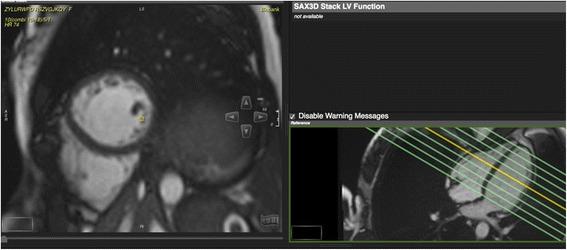

UK Biobank's cardiovascular magnetic resonance protocol.

METHODS/DESIGN: We describe the CMR protocol applied in UK Biobank's pilot phase, which will be extended into the main phase with three centres using the same equipment and protocols. The CMR protocol includes white blood CMR (sagittal anatomy, coronary and transverse anatomy), cine CMR (long axis cines, short axis cines of the ventricles, coronal LVOT cine), strain CMR (tagging), flow CMR (aortic valve flow) and parametric CMR (native T1 map).

方法/设计:我们描述了英国生物银行试点阶段所应用的CMR方案,该方案将在三个使用相同设备和方案的中心扩展到主要阶段。CMR方案包括白血CMR(矢状位解剖、冠状动脉和横断位解剖)、电影CMR(长轴电影、心室短轴电影、冠状位左心室流出道电影)、应变CMR(标记)、血流CMR(主动脉瓣血流)和参数化CMR(固有T1图谱)。